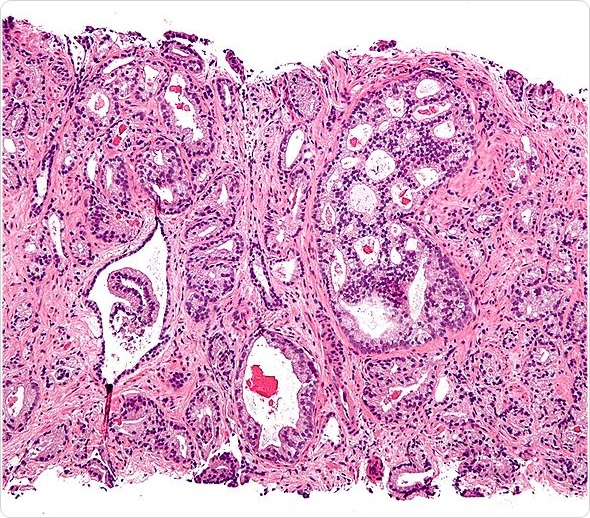

Micrograph showing prostatic acinar adenocarcinoma (the most common form of prostate cancer) Gleason pattern 4. H&E stain. Prostate currettings.